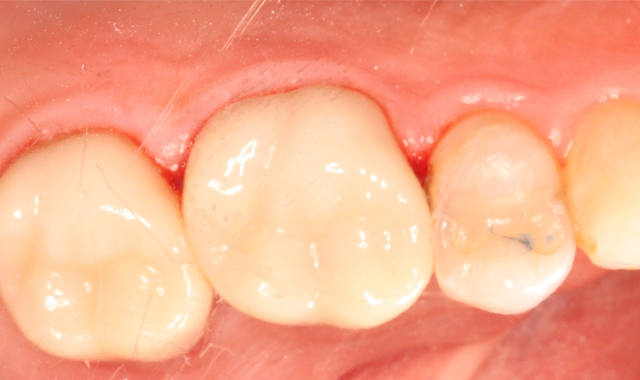

The patient was anesthetized and tolerated the crown preparations well. Both zirconia-style preparations were digitally scanned and those scanned impressions were sent to an off-site lab. Temporary crowns were fabricated and worn for two days. Upon return, the temporary crowns were immediately removed. Notice the healthy condition of the gingiva (Fig. 3).

At this point, the selection of what cement would work best enters the decision-making process. Taken into consideration is the height of the preparation and taper. Both preps are retentive. This allows the choice of either bonding or traditional cementing.

Given the three classifications of bonding mechanisms earlier mentioned, a self-etching adhesive resin cement, SoloCem® (Coltene), is selected. SoloCem offers a one-step bonding approach to final cementation that reduces the risk of contamination during the process and also includes the MDP and 4-MET(A) monomers that ensure good bond strength to the zirconia substrate - no additional metal primer monomer is needed (Fig. 4).

Fig. 3 Fig. 4

Both preparations were scrubbed with 2% chlorhexidine to remove any residual cement or debris. Both zirconia crowns were scrubbed with Ivoclean® (Ivoclar Vivadent) - a decontaminator - for 20 seconds, then thoroughly rinsed and air dried. A frosty internal surface appeared on both crowns.